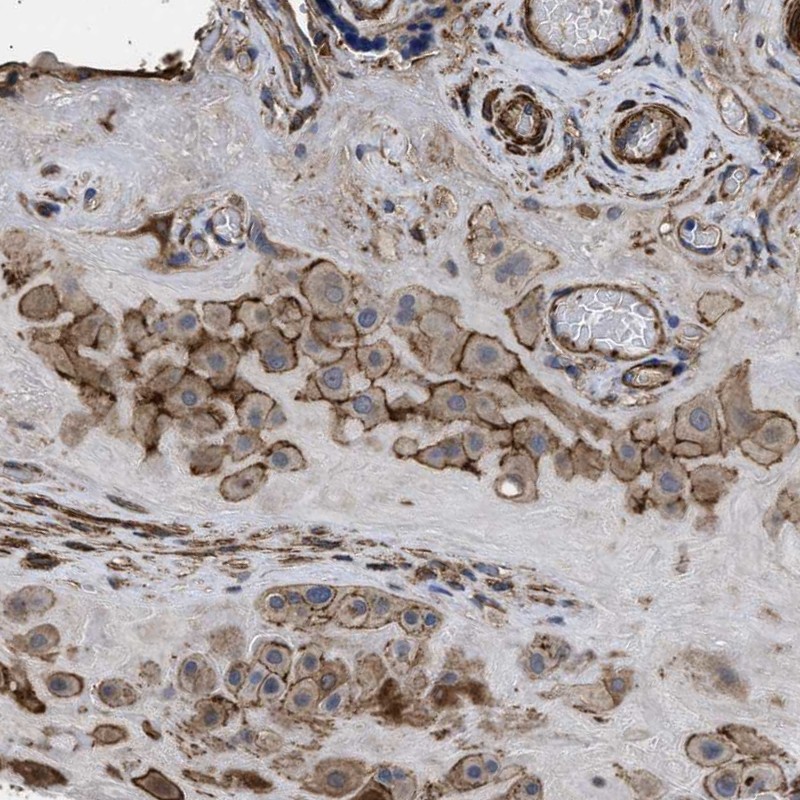

Immunohistochemical staining of human placenta shows membranous positivity in decidual cells.